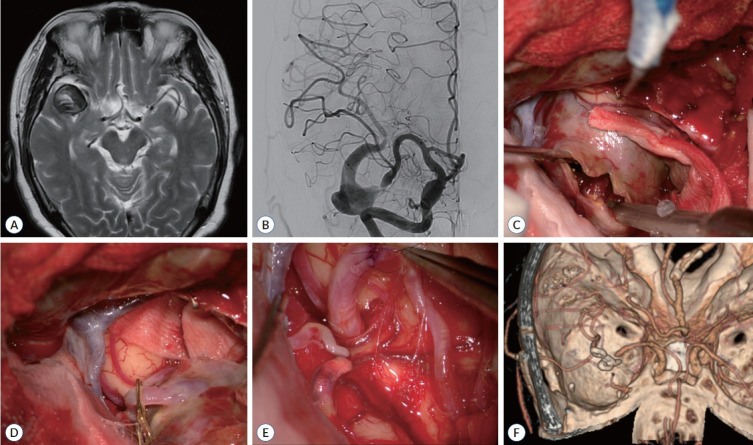

Abstract Image